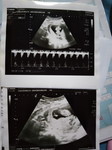

เจอถุงตั้งครรภ์เจอตัวอ่อน แต่ไม่เจอหัวใจ

สอบถามแม่ๆที่เคยมีประสบการณ์ทีค่ะ ไปฝากครรภ์ ตอน8วีค5วัน เจอถุงตั้งครรภ์เจอตัวอ่อนแต่ไม่เจอหัวใจน้อง หมอซาวผ่านหน้าท้องไห้ หมอซาวเจอขนาด7วีค5วัน หมอจะไห้อมยาใต้ลิ้นแต่แม่ขอรอดูซักอาทิตย์ หมอเลยไห้รอมาตรวจอีก2อาทิตย์ แม่ๆคนไหนมีประสบการณ์ มาบอกเล่าต่อกันทีค่ะ กังวลมาก อยากซาวผ่านช่องคลอดเพื่อจะได้เห็นชัดขึ้นเพราะแม่อ้วนแต่หมอยังไม่ซาวไห้🥺#ขอบคุณคำตอบค่ะ #ขอบคุณสำหรับคำคอมเม้นล่วงหน้าค่ะ